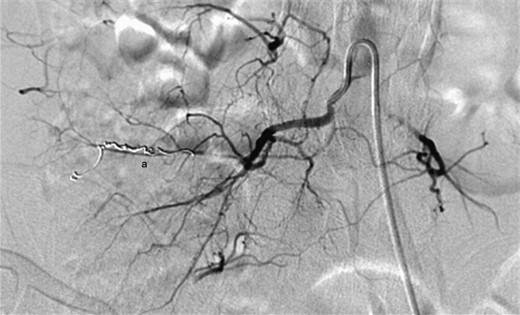

Digital subtraction angiography showing a small pseudoaneurysm originating from the peripheral aspect of the distal right lumbar artery (a).

Digital subtraction angiography demonstrating successful embolization of the proximal and distal entry points of the pseudoaneurysm using platinum microcoils (a).